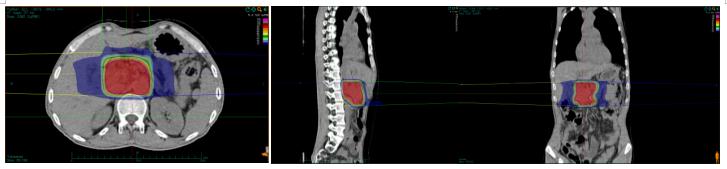

因胰腺病灶压迫十二指肠水平部导致高位消化道肠梗阻,引起胃潴留及进食后呕吐,患者入院后行营养管置管及胃肠减压,保证营养支持充足及胃排空状态前提下,于2020-12-29日开始碳离子治疗,剂量:55.2Gy(RBE),共治疗12次。治疗第7次疼痛明显缓解,治疗期间肿瘤标志物明显下降。治疗后一个月患者完全正常饮食,肿瘤缩小,治疗6个月后肿瘤坏死,活性完全消失。

胰腺癌碳离子治疗靶区计划